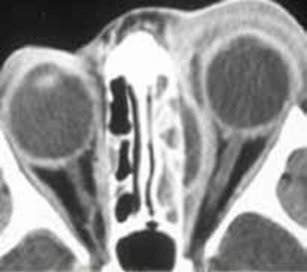

L’échographie abdominale réalisée objectivait une vésicule à paroi fine siège de plusieurs mini-calculs (Figures 1, 2).

La tomodensitométrie abdominale avec opacification confirmait cette cholécystite avec un foie hétérogène, siège de multiples microlésions arrondies hypodenses, rehaussées légèrement après injection de produit de contraste (Figures 3, 4).